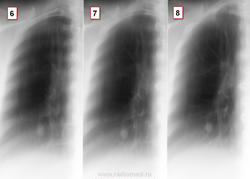

Снимки из серии "найти на боковой". Женщина 1948 г.р. Жалоб со стороны органов грудной клетки нет.Где тень на боковой проекции? К какому диагнозу склоняетесь? На днях будет ЛТ. ТМГ https://radiomed.ru/sites/default/files/styles/case_slider_image/public/user/16807/2_68.jpg?itok=PMWHQcLH https://radiomed.ru/sites/default/files/styles/case_slider_image/public/user/16807/3_42.jpg?itok=jjhsCDoN ID:46784 Fri, 25/04/2014 - 23:33 #1 алкс Offline Last seen: 10 years 6 months ago Joined: 24.10.2012 - 22:55 Posts: 2915 М.б. тутПриложения: Fri, 25/04/2014 - 23:38 #2 Сольвейг Offline Last seen: 3 years 11 months ago Joined: 05.02.2013 - 20:25 Posts: 2239 Ах, не успела. Тут, еще может в средней доле быть, -установка немного хромает. Рачок периферический, по-видимому, растет Fri, 25/04/2014 - 23:38 #3 NIL Offline Last seen: 3 weeks 1 day ago Joined: 25.11.2013 - 20:50 Posts: 18217 Да. Это она. Судя по гладкости и чёткости контуров, можно думать о доброкачественном новообразовании. Возможно, аденома.Приложения: "Слушай всех, прислушивайся к немногим, решай сам".© Fri, 25/04/2014 - 23:39 #4 Сольвейг Offline Last seen: 3 years 11 months ago Joined: 05.02.2013 - 20:25 Posts: 2239 А почему тмг не сейчас? Не сделали? Fri, 25/04/2014 - 23:57 #5 Dima Offline Last seen: 7 years 8 months ago Joined: 05.08.2012 - 17:39 Posts: 2467 Миргалина wrote: А почему тмг не сейчас? Не сделали?сделал, только карты открывать не хотелось сразу... Терпимость - это когда прощают чужие ошибки; такт - когда не замечают их. (Артур Шницлер) Sat, 26/04/2014 - 00:00 #6 Сольвейг Offline Last seen: 3 years 11 months ago Joined: 05.02.2013 - 20:25 Posts: 2239 Да открывайте уж, интересно же.Пожалуйста! Sat, 26/04/2014 - 00:15 #7 Dima Offline Last seen: 7 years 8 months ago Joined: 05.08.2012 - 17:39 Posts: 2467 Тень там где её и указали коллеги. Глазастые все, молодцы, а я вот долго искал...Приложения: Терпимость - это когда прощают чужие ошибки; такт - когда не замечают их. (Артур Шницлер) Sat, 26/04/2014 - 00:12 #8 Сольвейг Offline Last seen: 3 years 11 months ago Joined: 05.02.2013 - 20:25 Posts: 2239 Ну да, в 10-ке. Спасибо! Sat, 26/04/2014 - 10:03 #9 NIL Offline Last seen: 3 weeks 1 day ago Joined: 25.11.2013 - 20:50 Posts: 18217 Тень плотная. Может оказаться и гамартохондромой. "Слушай всех, прислушивайся к немногим, решай сам".© Tue, 29/04/2014 - 00:37 #10 lady.zhaneta Offline Last seen: 1 year 7 months ago Joined: 06.07.2011 - 21:54 Posts: 232 Спасибо от тех ,кто учится читая ваши комментарии, и от себя лично)

Ах, не успела. Тут, еще может в средней доле быть, -установка немного хромает. Рачок периферический, по-видимому, растет

Да. Это она. Судя по гладкости и чёткости контуров, можно думать о доброкачественном новообразовании. Возможно, аденома.

Тень там где её и указали коллеги. Глазастые все, молодцы, а я вот долго искал...

Ну да, в 10-ке. Спасибо!

Тень плотная. Может оказаться и гамартохондромой.